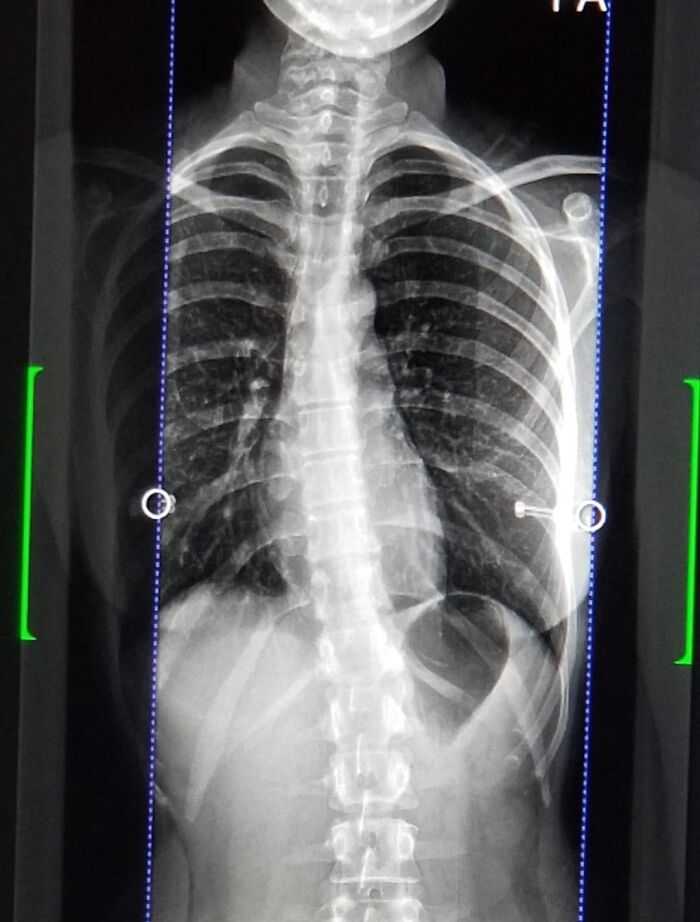

#22 Update: Reddit Called My Scoliosis With My Ribs! Went And Got An Xray And The Doctor Confirmed. Ive Got Physiotherapy Tomorrow. Thanks Reddit :)

Image credits: medical